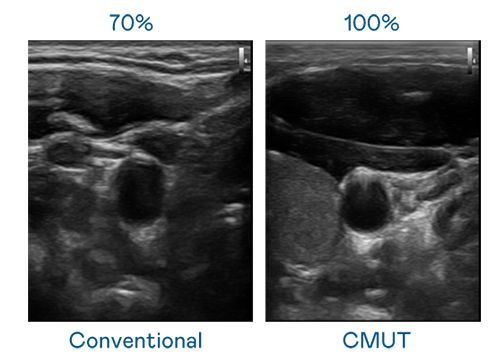

CMUT 技术是一种用电容式微机电元件来产生超音波讯号的技术。与传统 PZT 压电式技术相比,CMUT 频宽增加 30%,更宽频的超音波讯号让影像解析度大幅提升,是实现高影像品质医疗超音波扫描、促进精准医疗发展的关键技术。

超音波影像的解析度高低,首先取决于探头能发出的讯号频宽。球速体育 CMUT 可提供高清晰的超音波讯号,提供高频宽、高灵敏度、影像纹理细节更高的超音波影像,协助医护人员缩短影像判读时间及利用精准的医疗影像进行诊断。